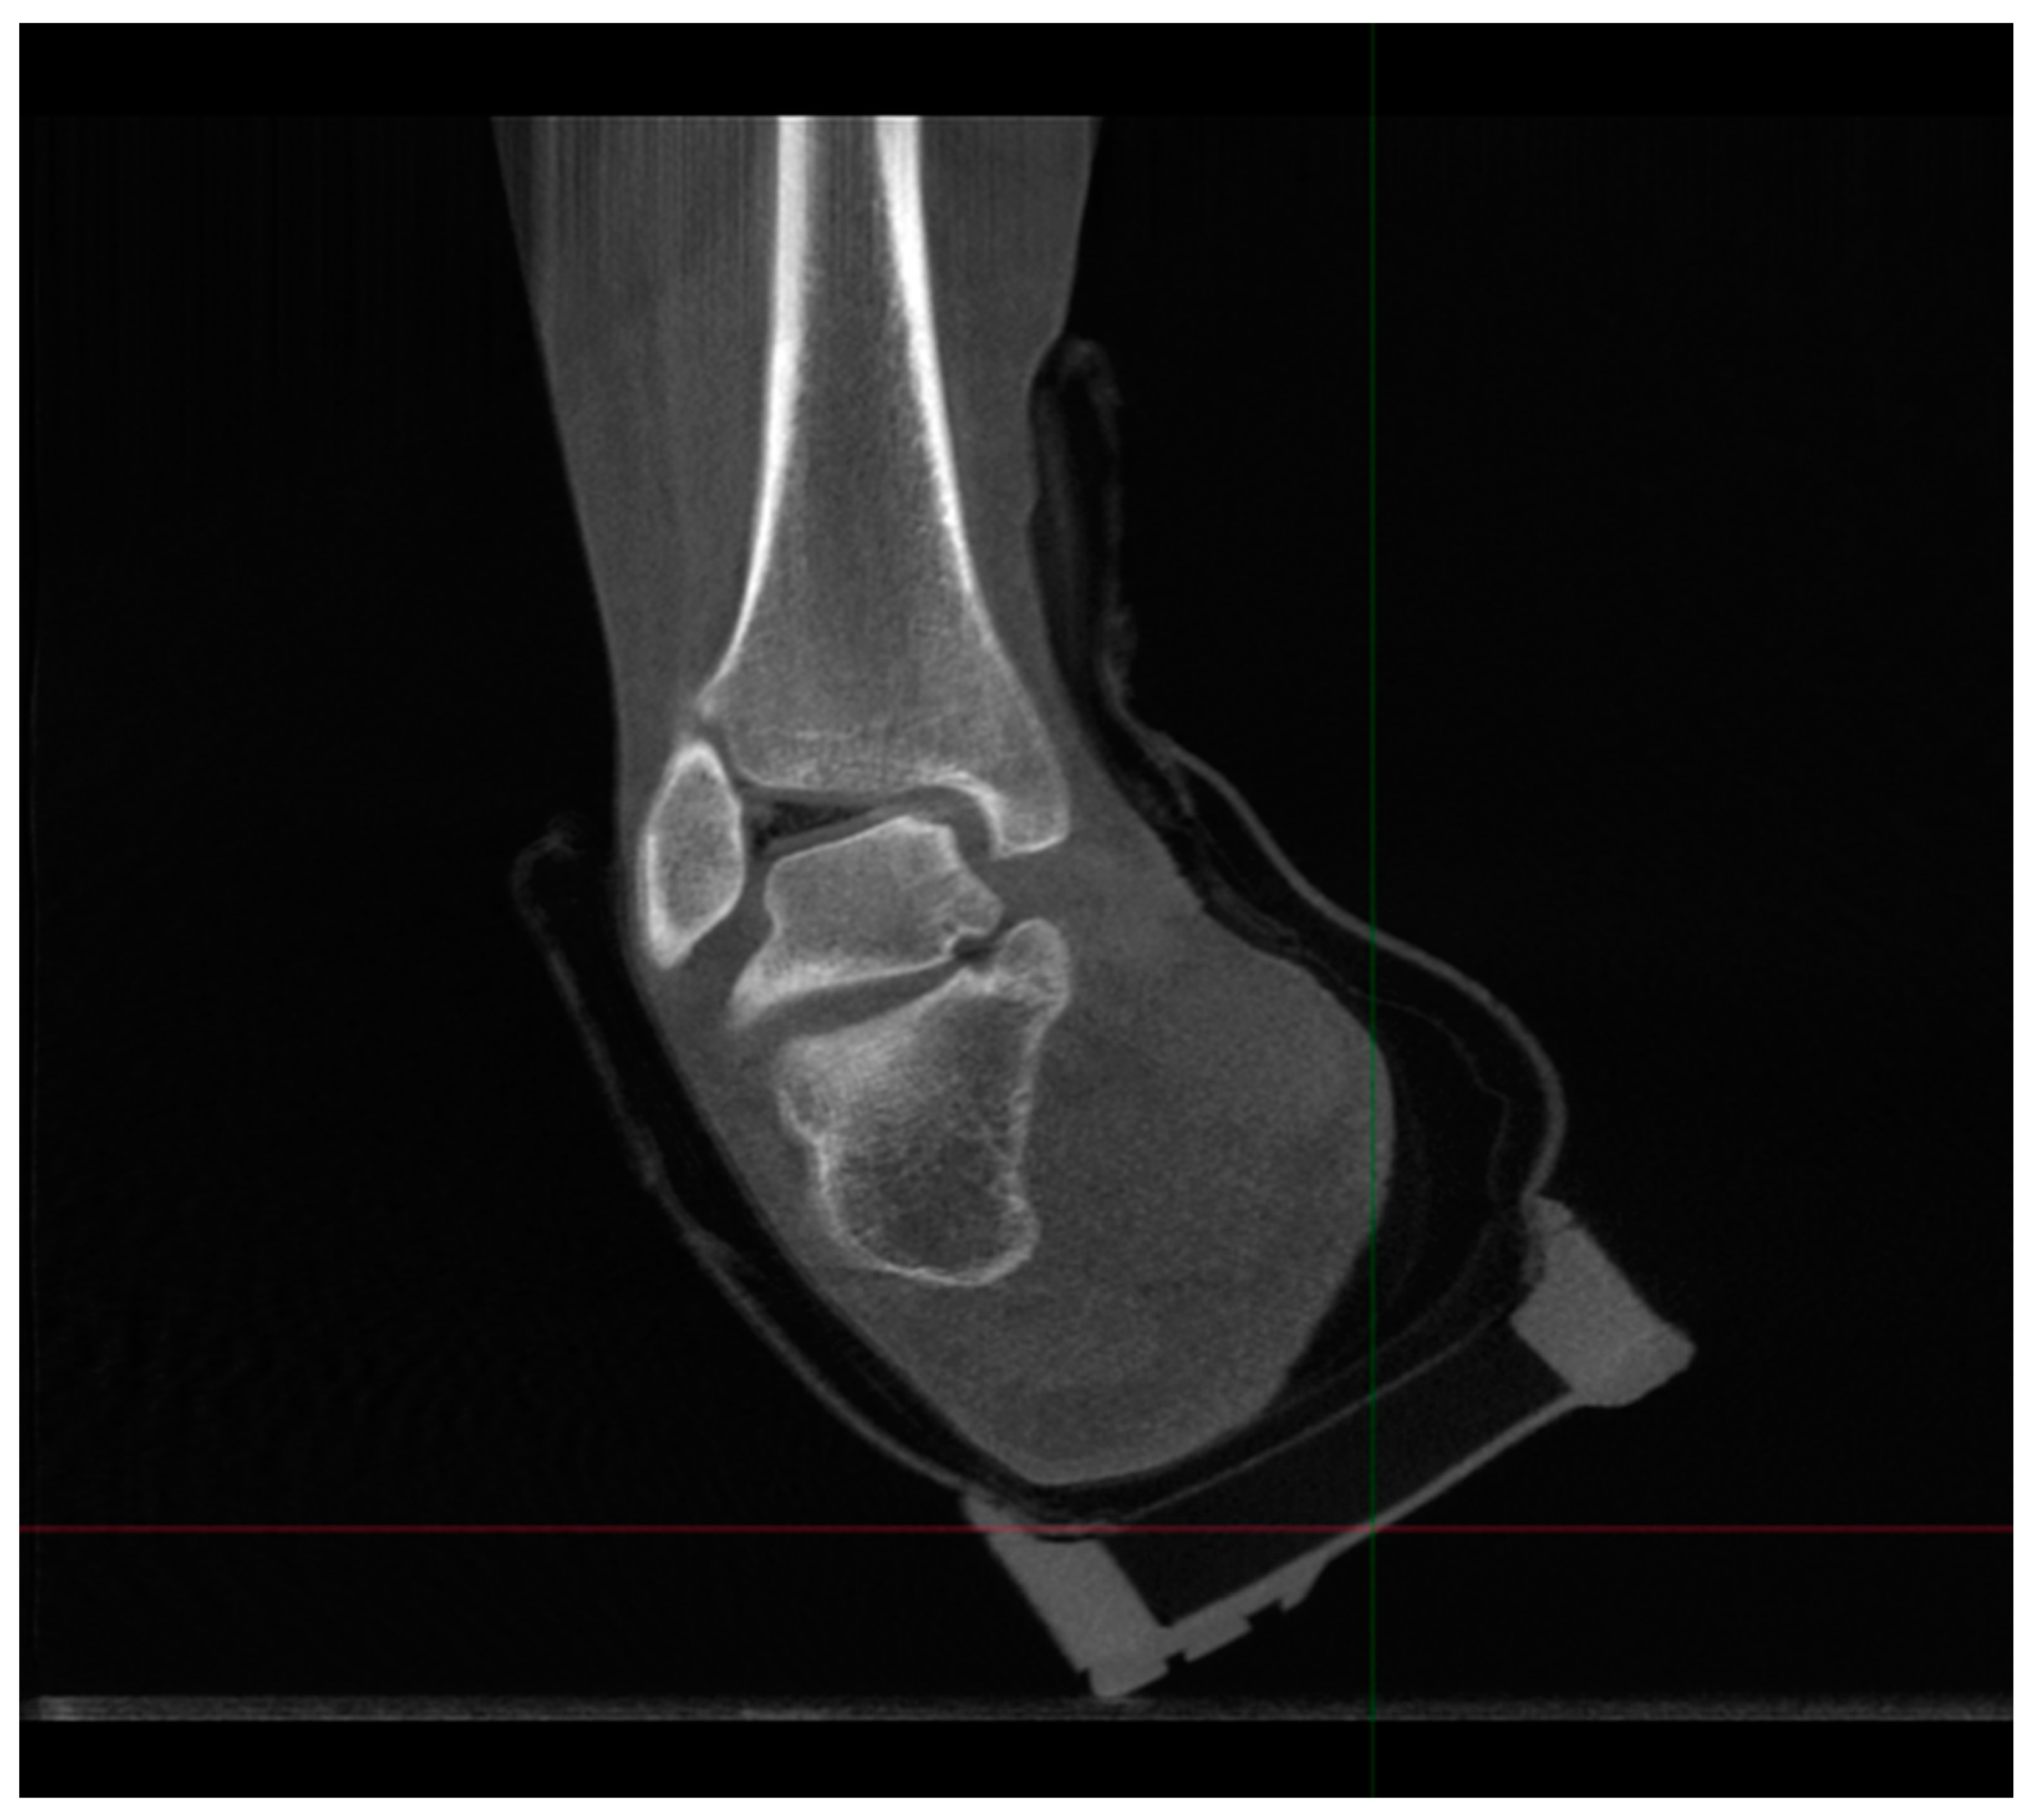

Recent Innovations Brought about by Weight-Bearing CT Imaging in the Foot and Ankle: A Systematic Review of the Literature

:1. Introduction

4.2.1. Description of Techniques for Image Acquisition